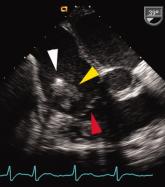

ArticleUnusual Cardiac Rhythm Device InfectionAuthor:Peter J. Cawley, MDPublish date: April 25, 2008Read More